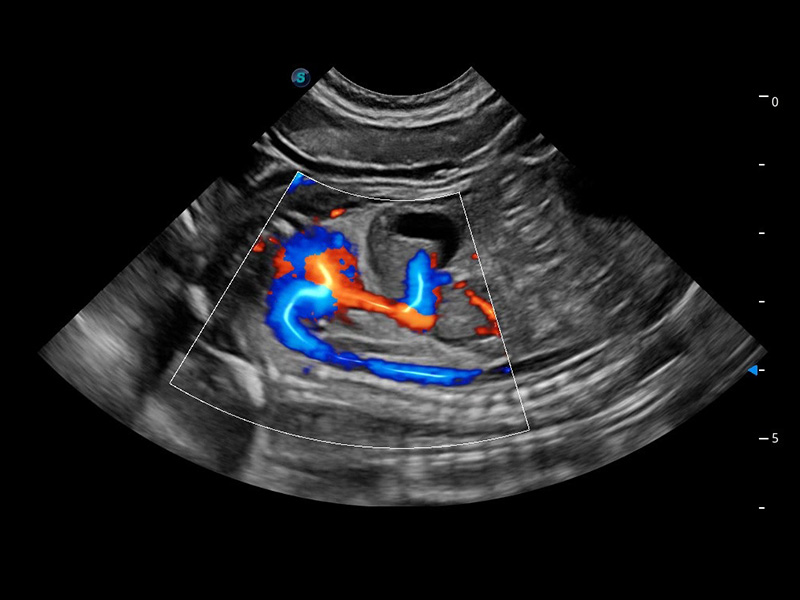

ProPet 60 作为一款高端台式动物超声设备,为动物医生的日常诊断提供了一系列贴合动物临床需求、解决临床实际问题的高级成像功能。凭借全系列高清探头,满足医生对腹部、心脏、生殖、浅表、肌骨等成像的所有需求,切实帮助您提升检查效率,提高诊断信心。

兽用彩色多普勒超声诊断系统

动物是人类最亲密的朋友和最值得信赖的伙伴。银河集团官网也一直致力于探索动物专用的超声影像解决方案。 全新推出的ProPet系列,是银河集团官网在动物超声影像智能化、专业化、精准化的一次跨越式革新。动物不能用言语来表述自己的不适,通过超声影像,ProPet系列搭建了动物医生与不同物种沟通的“桥梁”,为动物医生注入了“治愈之力”。